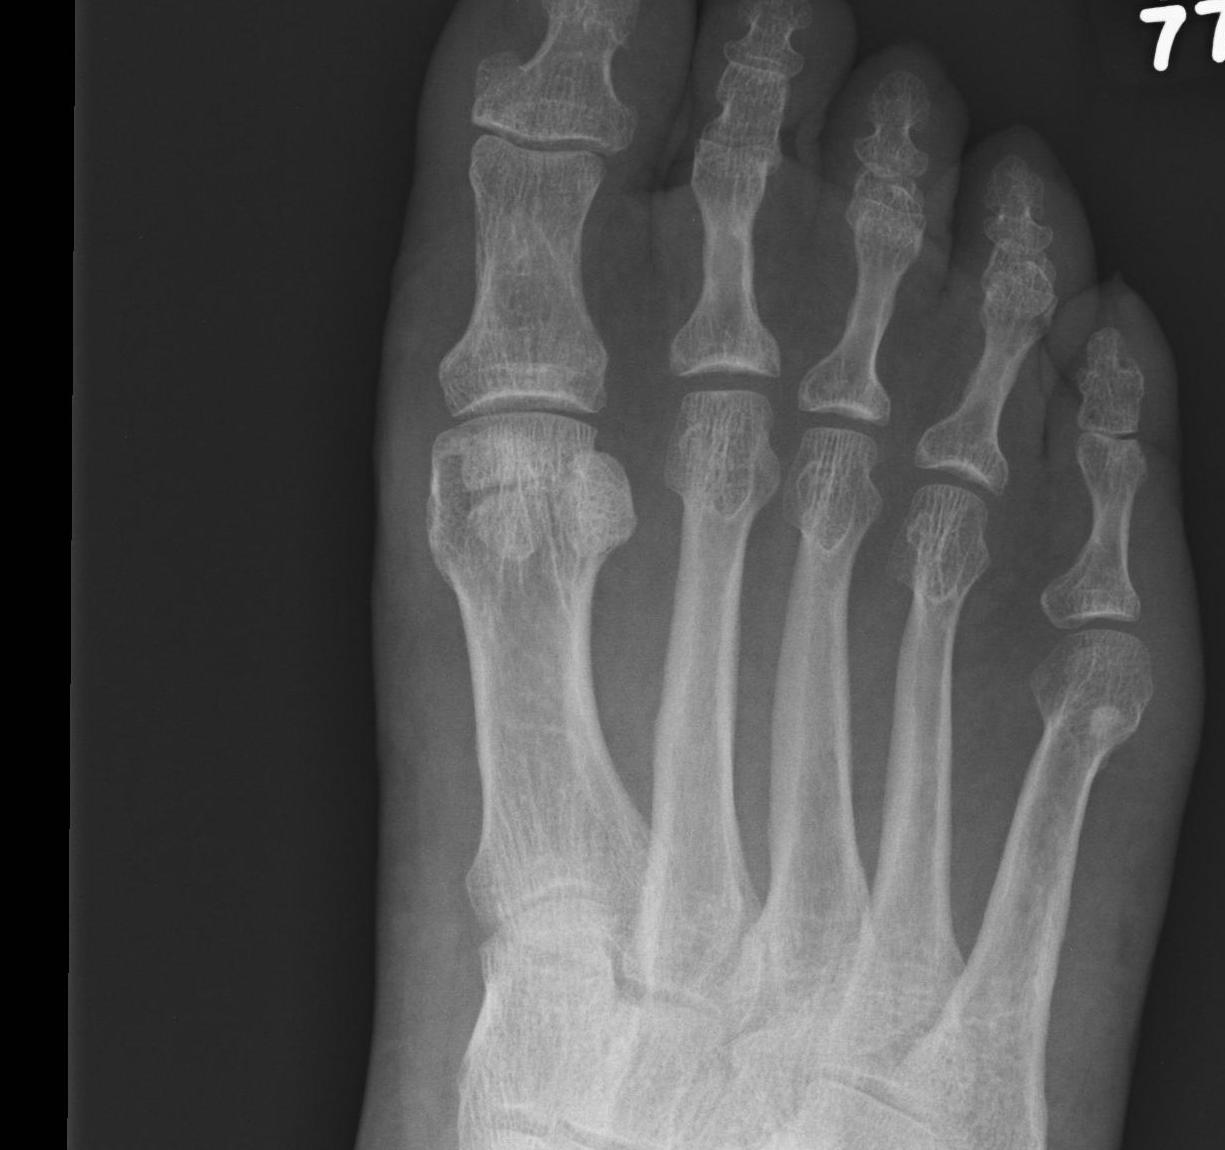

Sesamoid Bone X Ray Collection 2022 Sesamoid Bone X Ray Collection 2022

Sesamoid Bone X Ray

Sesamoid fracture | Radiology Reference Article | Radiopaedia.org Radiology Review - Sesamoid fracture | Axis Sports Med Toes (sesamoid view) | Radiology Reference Article | Radiopaedia.org Sesamoid | Radiology Reference Article | Radiopaedia.org Sesamoid bone - Wikipedia Sesamoid Bone X Ray